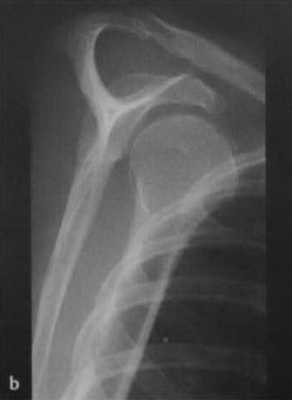

а, b Задний вывих плечевого сустава у женщины 45 лет после падения с велосипеда, (а) Рентгенологическое исследование правого плечевого сустава. Суставная щель в прямой проекции не визуализируется, плечо ротировано медиально.(b) Y-проекция четко демонстрирует задний вывих.

- Рентгенологическое исследование в двух проекциях: прямая тангенциальная (касательная) проекция суставной полости и чрезлопаточная проекция.

Передний вывих: головка плечевой кости расположена кпереди и книзу, обычно ниже клювовидного отростка; в редких случаях она может находиться на нижней границе суставной полости.

Задний вывих: головка плечевой кости перекрывает границу суставной полости; суставная щель не визуализируется.